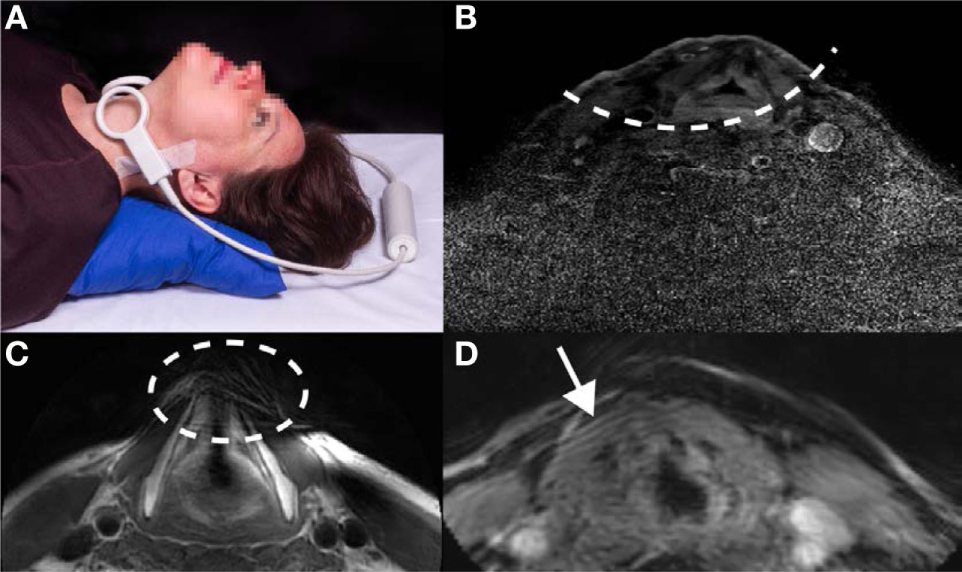

Historically, computed tomography (CT) has been the imaging modality of choice, particularly for RT (10). CT is a robust modality due to very short acquisition times and high signal-to-noise ratio (SNR), but is limited in its utility since differentiation between healthy tissue and tumors can be difficult (10, 11). Imaging the larynx using MRI became a useful alternative to CT in the late 1980s and early 1990s primarily due to the development of local surface coils, which enabled higher resolution imaging over a field-of-view, which could be localized to the larynx (12–15). The lack of ionizing radiation, greater inter-tissue contrast, and multiplanar imaging capabilities were all advantages of MRI over CT, but long acquisition times limited the spatial resolution that could be achieved. Only when parallel imaging became available to reduce MRI acquisition times was it possible to achieve high spatial resolution in a realistic scanning time (16). However, laryngeal imaging is still problematic. Current MRI protocols in early glottis carcinoma primarily use general purpose commercial local surface coils (which can also be combined with a head coil), or phased array head/neck coils (8, 17–23). As these coils (for example two loops as shown in Figure 1A) are not specifically designed for laryngeal imaging, correct positioning centered on the vocal cords is critical, and needs to be done carefully and precisely by an experienced technician. Problems also arise with different-sized necks, which require a different physical separation of the coils. If the coils are placed too close together then they couple to one another, reducing the signal-to-noise, and also result in too small a field-of-view, a reduced penetration depth, and poor parallel imaging performance (including the possibility of fold-back artifacts): a typical example is shown in Figure 1B. If the loops are placed too far apart, or the patient has a large neck, signal voids within the larynx may occur, as shown in Figure 1C. In addition, the separate loops are prone to displacement during the examination, which increases the patient handling time and may induce patient discomfort.

Figure 1

Illustrations of the challenges associated with current approaches to laryngeal magnetic resonance imaging. (A) Two individual, commercial circular receive coils, each with a diameter of 4 cm, are placed around the larynx. Positioning in this particular setup is critical for imaging the larynx and can be experienced as uncomfortable by the subject since the loops have to be held firmly in place with tape and/or velcro straps. Written informed consent was obtained from the subject for publication of this photo. (B) Images acquired with a limited penetration depth due to incorrect coil positioning, (C) images showing signal voids in the anterior part of the larynx due to incorrect coil positioning, and (D) images showing movement artifacts due to subject breathing.

Even if proper positioning of the coil has been performed, reconstructed images of the larynx often suffer from patient-related artifacts, which in some cases render images non-useful for diagnosis. One common cause is movement of the larynx during data acquisition, as shown in Figure 1D. Movement is unavoidable during the scanning protocol, as breathing causes the vocal cords to move. Swallowing, which moves the full larynx up to several centimeters in the feet–head direction, may occur and can produce severe image artifacts. In addition, pulsation in the blood vessels in the neck commonly creates flow artifacts, which can extend into the larynx region, depending on the imaging protocol used.